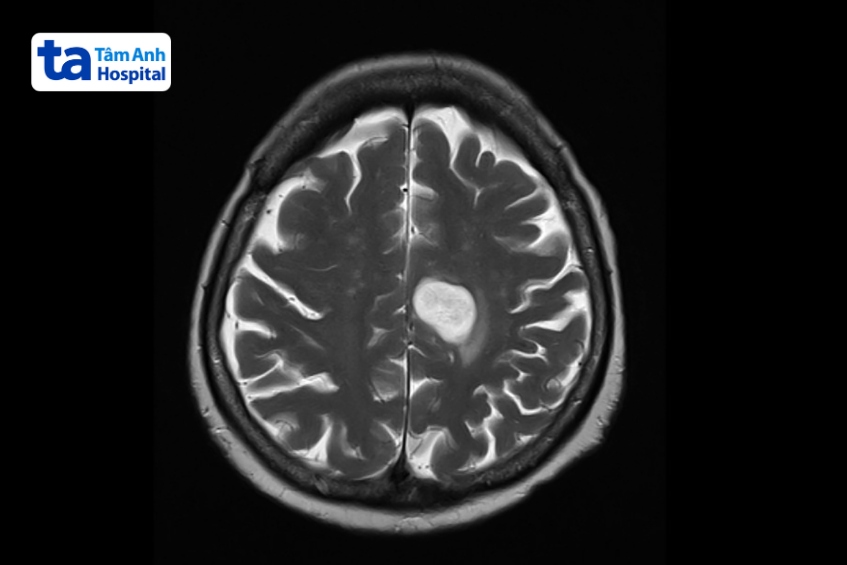

Bệnh u não ở trẻ em là tình trạng các tế bào não phát triển bất thường, hình thành khối u xuất hiện bên trong tổ chức não hoặc mô lân cận. Khi khối u não gia tăng kích thước sẽ chèn ép các vùng lân cận của não và gây ra các dấu hiệu u não ở trẻ em như đau đầu, nhìn mờ, tê yếu cơ thể, buồn nôn…

Bệnh u não ở trẻ em có thể lành tính hoặc ác tính (ung thư). Khối u trong não ở trẻ có thể là khối u nguyên phát (bắt nguồn tại não) hoặc u não thứ phát (còn gọi là khối u di căn não, khối u bắt đầu từ nơi khác sau đó lan đến não). (1)

Để có thể chẩn đoán bệnh u não ở trẻ em (phân loại, vị trí, mức độ của khối u), bác sĩ sẽ thăm khám lâm sàng và có thể chỉ định một số xét nghiệm cận lâm sàng bao gồm: